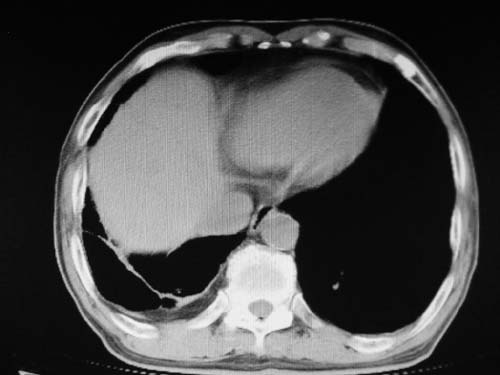

结合患者年龄,不除外左下肺扩张性动脉瘤,建议胸透是否有扩张性博动,以便确诊。

肺动脉高压,左肺动脉瘤样扩张。

)考虑肺动脉扩张,右心室增大,主动脉弓段正常位弓后段明显变小(不会是动脉导客未闭吧,不知患者有何症状病史)0。2)右肺上叶继发性肺结核。3)右侧胸膜增厚、钙化,左侧胸膜反应。